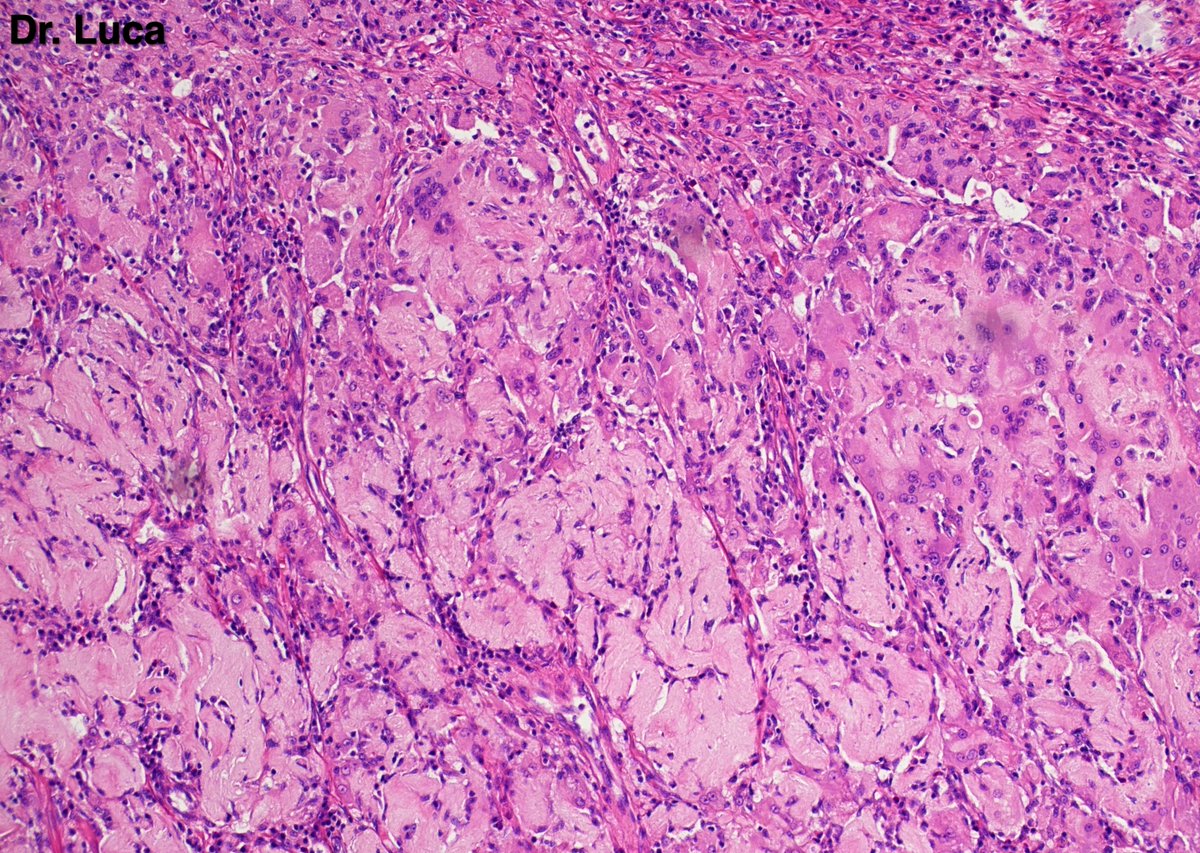

@Pathmath1 @SumantaDas_7 @PoloniaAntonio @ivanaspath @AnapathResident @bansar7 @goziemnweke @Teclis82 @Dr_Brian_Cox @DrBMcGinn @ariella8 @nusrat_xahra @DrRusella_Mirza @glinglerimek @kis_lorand @Venkateshgilly2 @DrBonita16 @DrPayelMondal @DrGeeONE @anjuthevirgo @niki_2389 @pepeheffernan @AngeloCassisa @NeoCrazee @TristanRutland7 Yes, it's a cancer with PNI...I show you the "superficial" layer of this cancer...what is the cancer? and what is the organ? #Pathology #GIpath #PathTwitter #PathResidents #pathboards